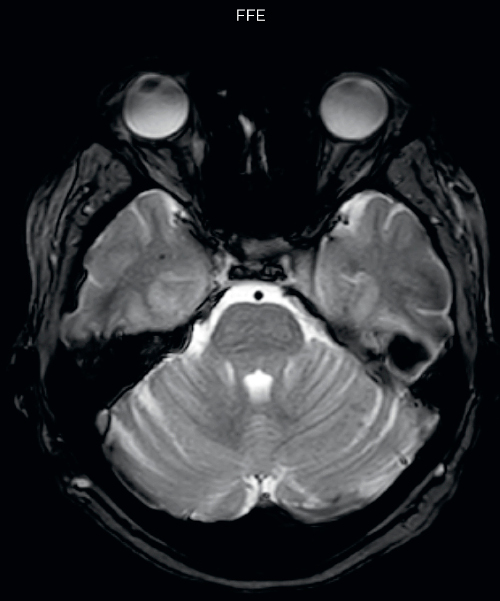

The SWIp sequence offers high resolution 3D susceptibility weighted brain imaging, which helps to visualize deoxygenated blood or calcium deposits. In combination with other clinical information, it may help in the diagnosis of various neurological pathologies

“With SWIp we are basically looking for blood byproducts. It is a sensitive method for visualizing small lesions containing deoxygenated blood. In our comparison, SWIp images are vastly better than gradient echo imaging, there’s no question of that anymore.” “We find the SWIp images very useful in three areas in particular. In patients with a history of hypertension, it offers clear visualization of hemosiderin deposition from hypertensive hemorrhages. We certainly see a greater number of foci of hemosiderin deposition on the SWIp images than on the T2* gradient echo images. In addition, it also helps us visualize amyloid depositions in patients with amyloid angiopathy.” Dr. Nickerson mentions trauma patients are the third large area where SWIp is useful. “We benefit from SWIp in trauma patients, certainly in cases with diffuse axonal injury and shearing injuries. Our study shows that SWIp usually provides us better visualization,” he says. “Apart from these three, SWIp also helps us to beautifully depict the normal venous anatomy in patients with venous outflow issues or vascular congestion. In some cases, we have seen downstream effects of arterial problems. And in patients with vascular malformations we have seen deposition of blood products associated with those.”

“We switched over entirely. SWIp is now included in all our routine brain exams. We developed two different SWIp sequences: a high spatial resolution (0.5 x 0.5 mm) version that takes 5.5 minutes and our fast SWIp that takes just three minutes. Only in patients that are moving tremendously we occasionally still acquire a gradient echo sequence.” “For us, SWIp use has resulted in more diagnostic confidence when small lesions, such as small shear injuries, vascular malformations, or minute amounts of calcification, need to be detected,” says Dr. Nickerson. “Our physicians greatly value the SWIp images. When we get patients transferred from other facilities with SWIp missing from their exam, we have several neurologists and neurosurgeons who order a new MRI exam because they want to see the SWIp images.”

Gradient echo imaging and SWIp are compared in a patient with radiation-induced foci of hemosiderin deposition. A greater number of small foci is seen on the SWIp image. Ingenia 3.0T